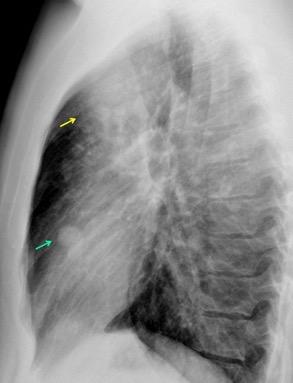

T. mixto de células germinales del testículo izquierdo

Nódulos pulmonares múltiples. (flechas verdes). Masas paratraqueales. (flechas amarillas). Dudoso ensanchamiento retrocrural (flechas negras). sigue….

Ttawfik A et al. Trans-diaphragmatic Pathologies: Anatomical Background and Spread of Disease on cross-sectional Imaging. Current Problems in Diagnostic Radiology. 2021.

T. mixto de células germinales del testículo

izquierdo Metástasis pulmonares. (flechas verdes). Ganglios paratraqueales. (flechas amarillas). Ganglios retroperitoneales (flechas negras)

Tawfik A et al. Trans-diaphragmatic Pathologies: Anatomical Background and Spread of Disease on cross-sectional Imaging. Current Problems in Diagnostic Radiology. 2021.